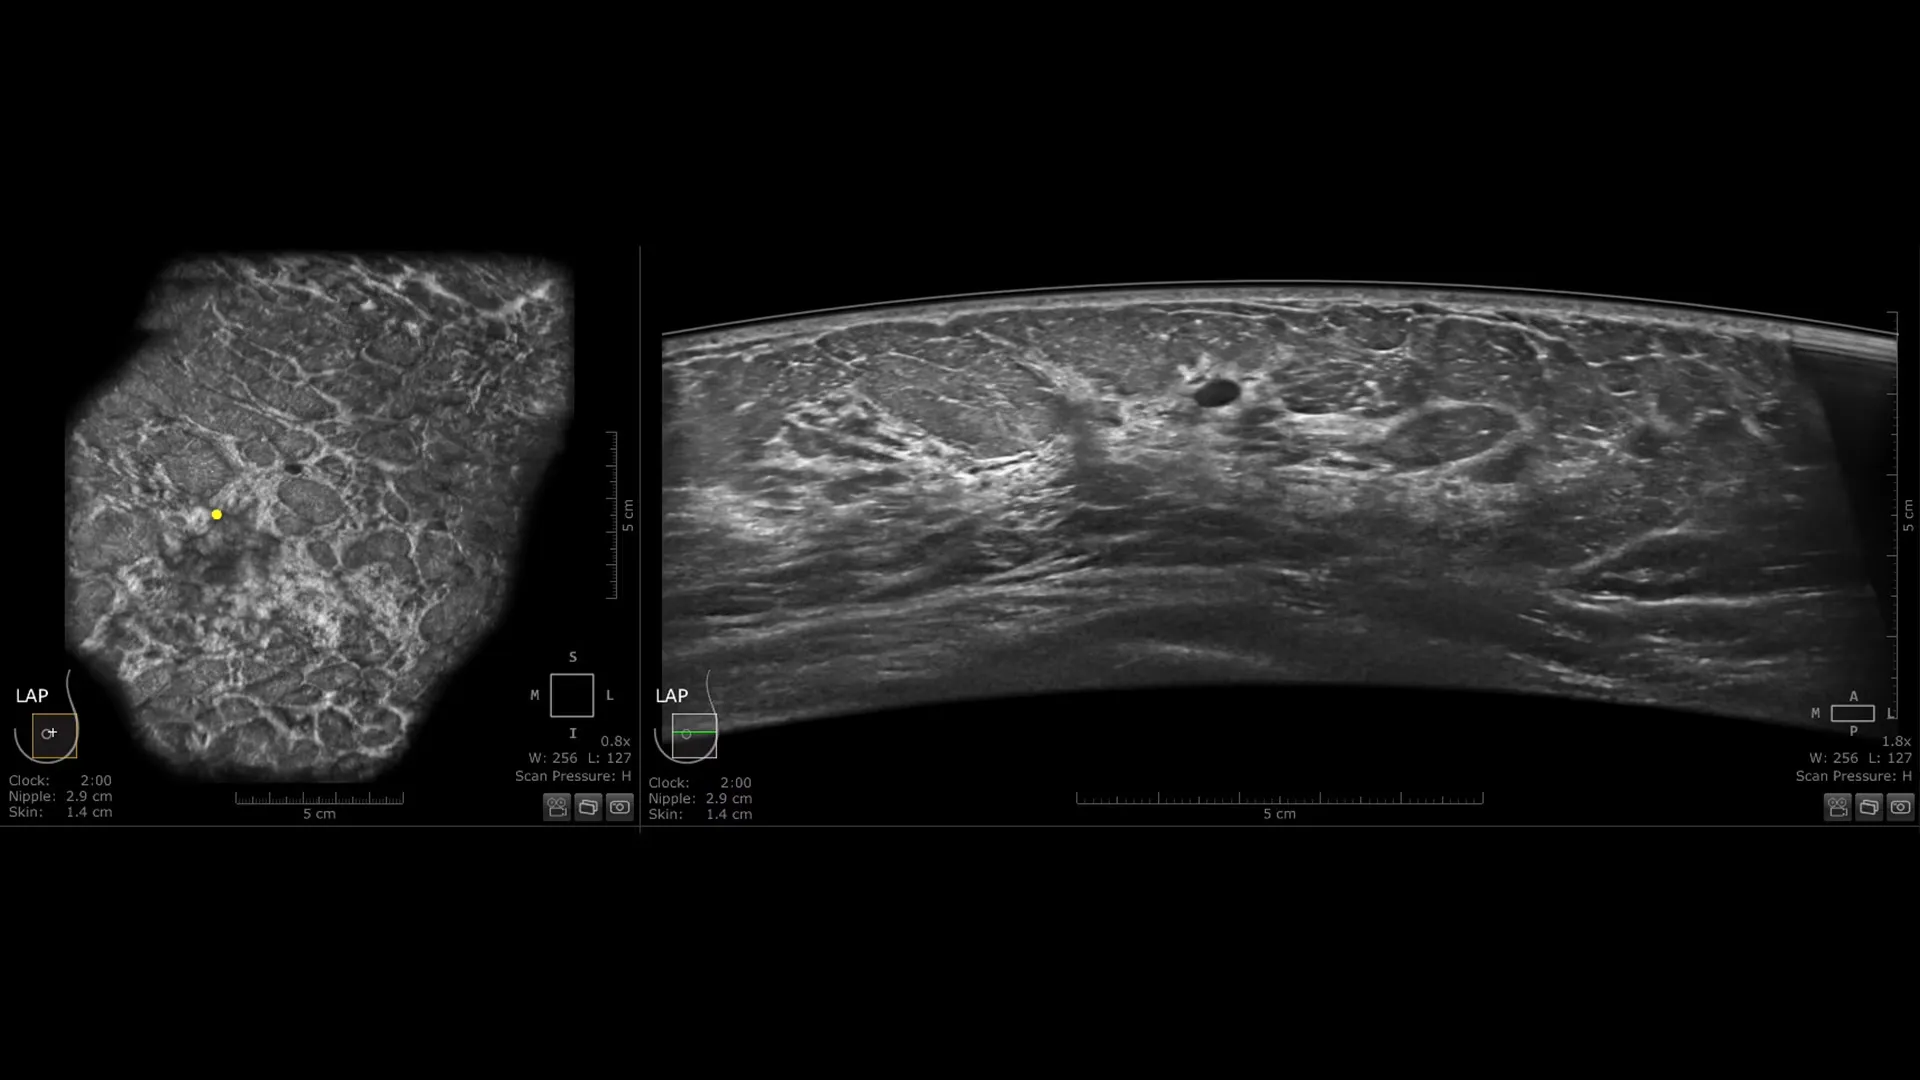

Invenia ABUS Premium osmišljen je za visoku propusnost pacijentica i iznimnu kvalitetu prikaza, pružajući visoku razinu dijagnostičke sigurnosti. Zahvaljujući inovativnom dizajnu, sustav je jednostavan za korištenje, reproducibilan, neovisan o korisniku, standardiziran te omogućuje očitanje nalaza s bilo koje lokacije.

Nova Reverse Curve™ sonda za poboljšane performanse

Njezin blago zakrivljen oblik duljine 15,3 cm prati prirodnu konturu dojke, povećavajući udobnost pacijentice* i osiguravajući potpuni kontakt za sveobuhvatnu pokrivenost. Unaprijeđena kvaliteta prikaza* dodatno povećava dijagnostičku sigurnost pri očitanju ABUS pregleda.

Centralizirano očitanje – bilo gdje, uz Invenia ABUS Viewer s AI Assistantom

Učinkovit radni proces Invenia ABUS Viewer sustava, uz AI Assistant**, omogućuje liječnicima brzo pregledavanje, interpretaciju i arhiviranje nalaza — čak i na daljinu.